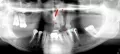

Здравствуйте. Просьба ответить, есть ли на снимке на нижней семерке слева киста. В настоящее время зуб удален. Нарушена чувствительность слева подбородка и губы. Врач утверждает, что киста проросла в нижнечелюстной канал, в этом причина. Была одновременно с удалением проведена имплантация шестерок нижних и слева за удаленной семеркой также установлен имплант (на месте восьмерки). Действительно ли была киста или причина неврита в имплантах (два из них на 0,5 мм выходят в канал). Имплантация была проведена 25.11.2013 г. и удаление зуба также.

Добрый лень. Кисты я не вижу. Онемение может быть связанно как по причине не корректной установки имплантатов так и от анестезии. Выложите снимки с имплантатами и я вам все расскажу. Всего доброго.